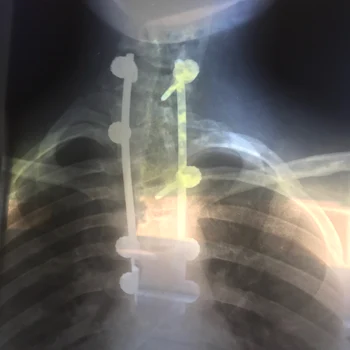

scolioza, evidentiata in radiografia publicata de Printesa Eugenie